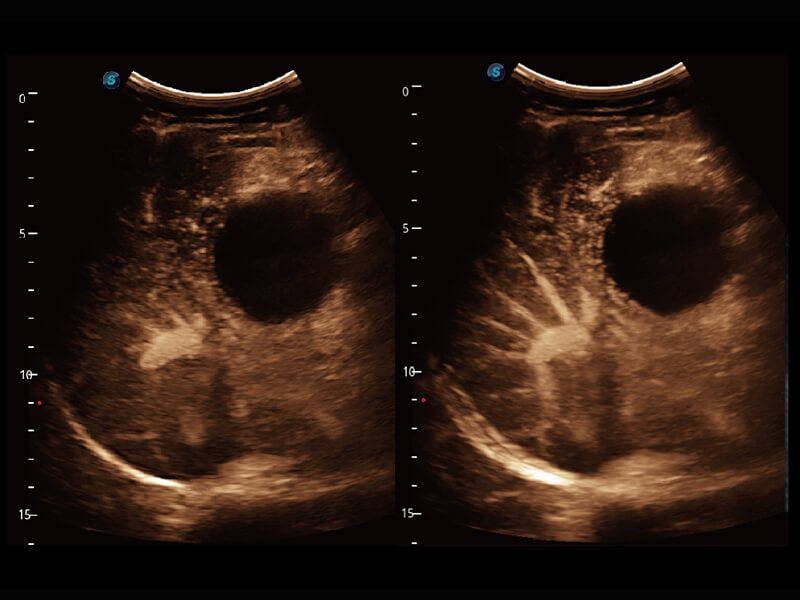

S60探头工艺,从前端信号处理每一个环节采集无损声学数据,真实还原组织原貌,再现解剖细节。